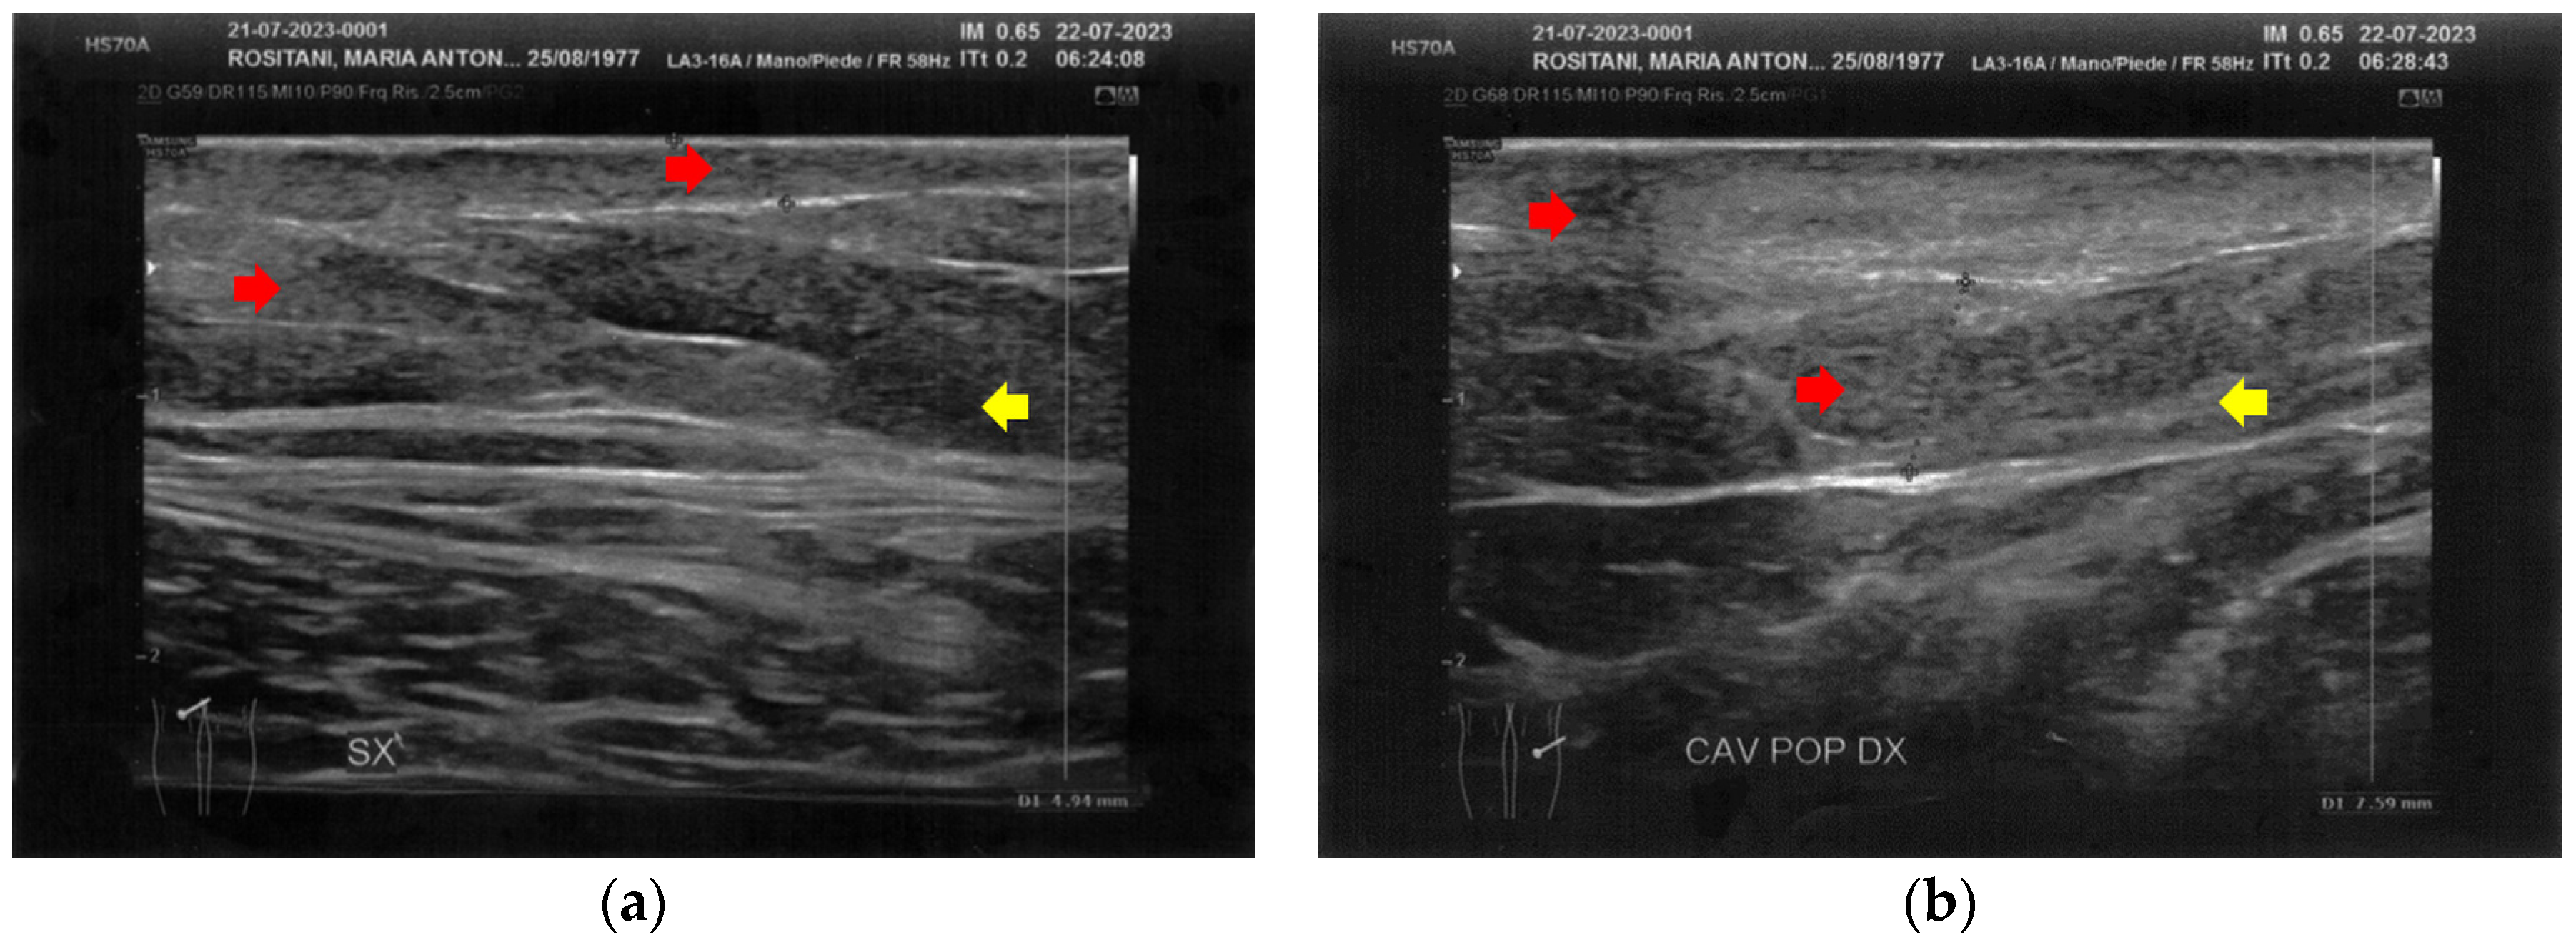

3.1. Basal Imaging Evaluations

3.2. Imaging Evaluations After the Treatment